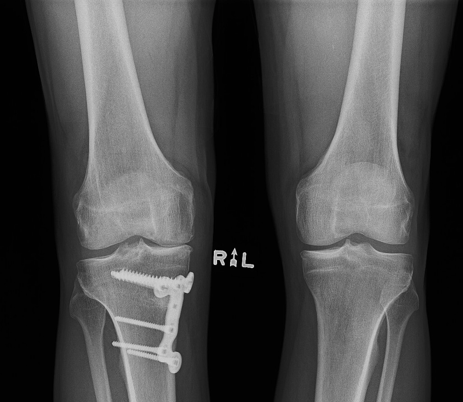

BJI Research Spotlight: Assessing Joint Health After Osteotomy

March 24, 2026A study with contributions from BJI Members investigated how realigning the knee through high tibial osteotomy reshapes joint health by tracking changes in inflammation and cartilage using synovial...